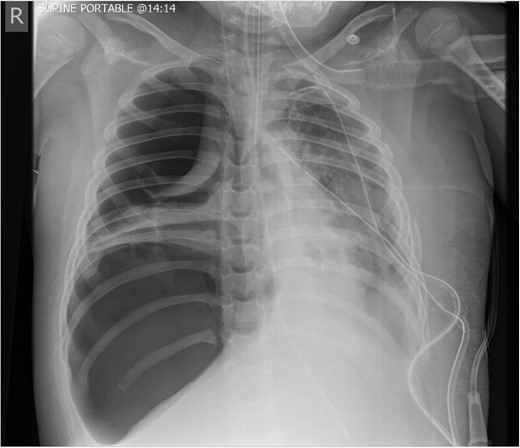

The initial chest radiograph revealed a possible diaphragmatic hernia and the patient was transferred to our institution for further investigation. The chest radiograph on arrival demonstrated a large air filled cavity at the left lung base. Further smaller cystic cavities were seen medially at the left base and right mid zone. The possible differential diagnoses included lung abscesses or diaphragmatic hernia (Fig. 1).

Chest radiograph on admission: a large air filled cavity at the left base. Further small cystic cavities seen medially at the left base and right mid to lower zone.